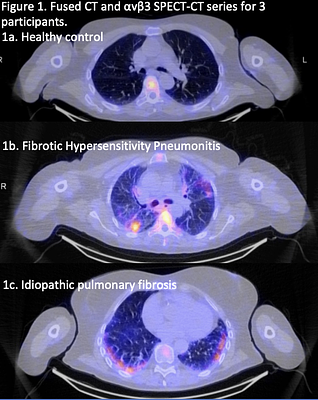

FDA Fast-Tracks Novel Imaging Agent for Lung Disease Diagnosis